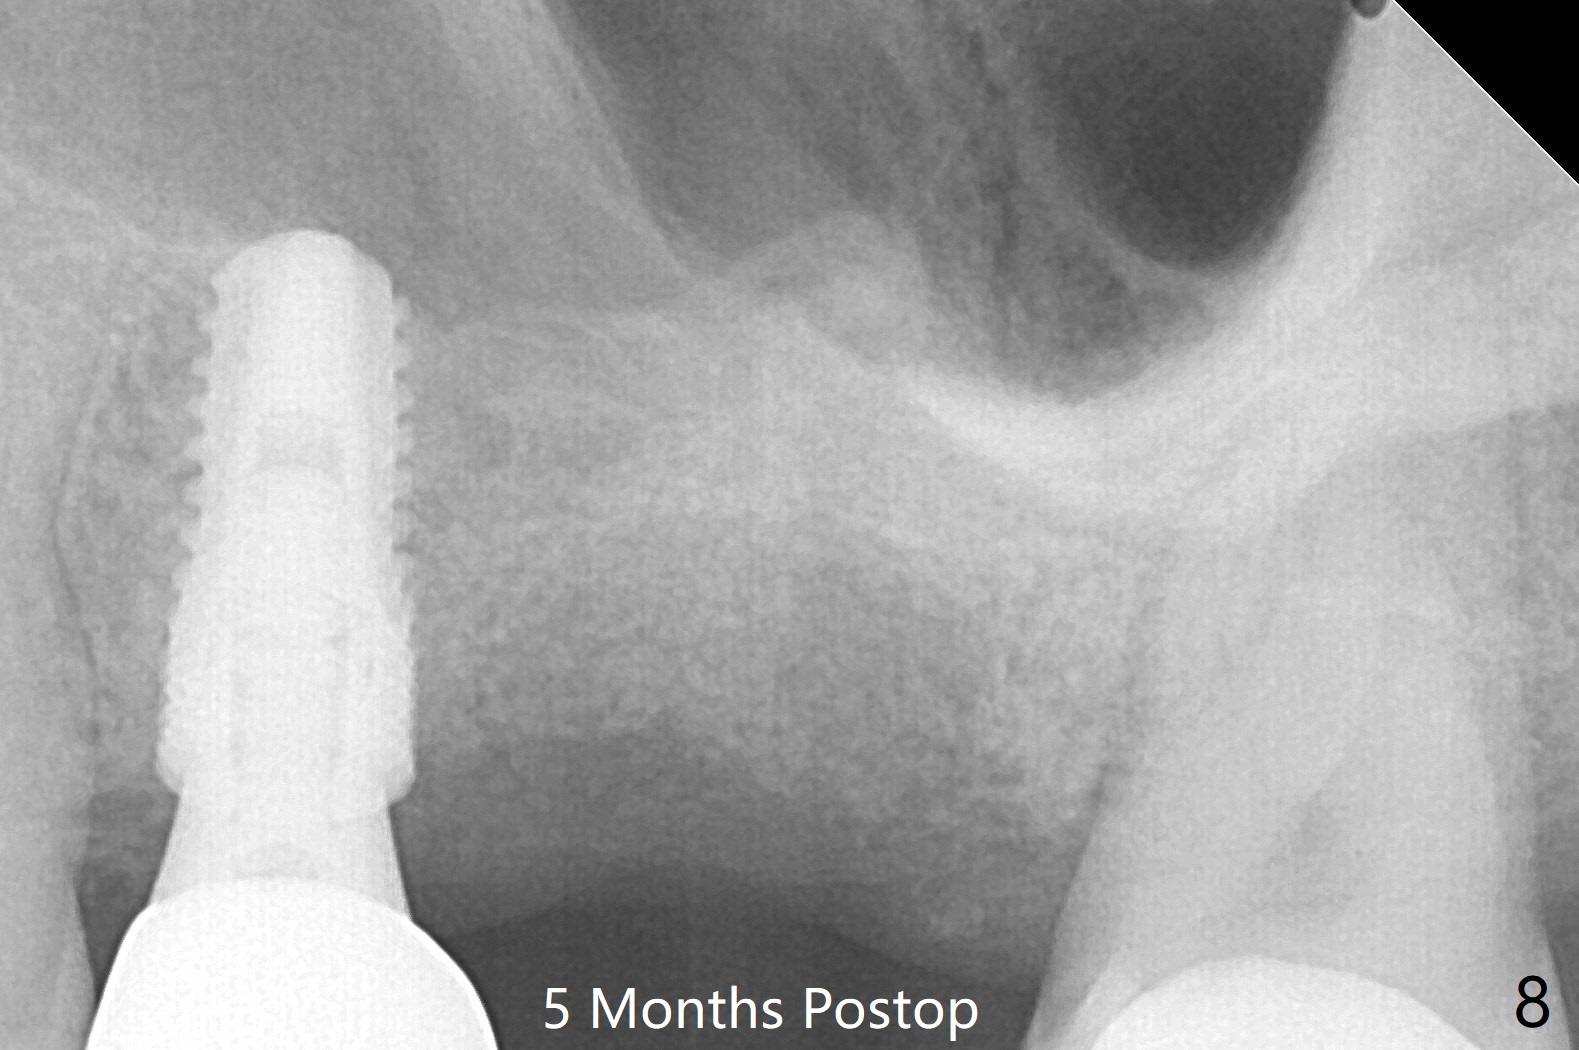

左上六拔除后,近中颊侧窝尤其大,与上颌窦相通(图一 *),而中隔比较尖,截除后还显得窄(图一,二:S),不太适合即刻种植。放置一块PRF膜于近中颊侧窝修补上颌窦,然后放置粘性骨块,好像有上颌窦提升迹象(图三:*(箭头:近中颊侧骨板缺失)),用骨粉填满其余牙槽窝(图四),覆盖另外一块PRF膜以及Cytoplast(不可吸收膜),用PTFE缝线(也不可吸收,与膜是同一个材料,非常柔软,好打结)缝合(图五)。最后使用牙周敷料。后者术后八九天脱落,病人术后十二天复诊,不可吸收膜腭侧有些外翻(图六箭头),伤口愈合尚可,没有骨粉丢失迹象,反复交代口腔卫生。再过三周撤除不可吸收膜。其实三周后膜自己脱落,病人回来撤去剩余缝线(图七),新鲜肉芽组织形成。术后5个月牙槽嵴和角化龈宽,骨高度尚可(图八),密度差些(图九,750单位),植体应该是4.5x8.5 或者 10 毫米,少量上颌窦提升。